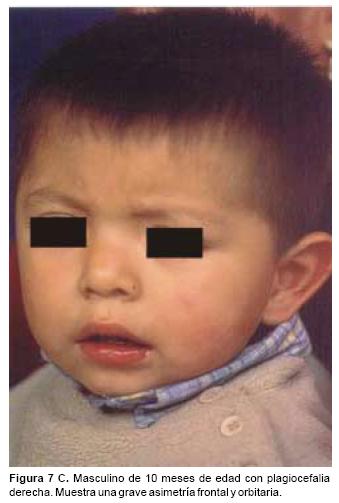

También los controles radiológicos durante el proceso de distracción mostraron que no se produjo la creación de espacios muertos intracraneanos durante los avances. En todos los pacientes con sinostosis bicoronal el avance frontoorbitario produjo excelentes resultados estéticos dando una nueva forma a la región frontal y proyectando mejor el reborde supraorbitario. En los niños con enfermedad de Crouzon y síndrome de Apert, se corrigió en forma muy satisfactoria el exorbitismo al resolver las graves exposiciones corneales (Figuras 5 A, B, C, D, E, F, G, H), en los que se utilizó el avance simultáneo del tercio medio, este cambio óseo corrigió muy satisfactoriamente la retrusión del mismo, ampliando la vía aérea y resolviendo en muchos casos grandes problemas ventilatorios durante el sueño (Figuras 6 A, B, C, D, E, F). Los pacientes con plagiocefalia corrigieron significativamente la deformidad frontoorbitaria y los tejidos blandos suprayacentes se adaptaron a la nueva estructura ósea. La clásica órbita de arlequín de estos niños producida por la sinostosis del frontal con el esfenoides, inmediatamente se ve corregida en su forma y su configuración se hace muy similar con la órbita contralateral (Figura 7)(Fig. 7a, 7b, 7c, 7d, 7e, 7f, 7g) (Cuadro II).